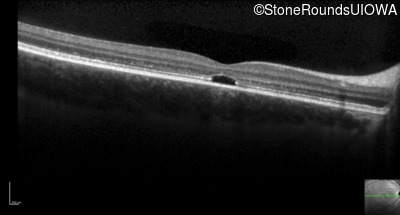

Optical Coherence Tomography - Left - 20/80 -1

Exemplar / OCT Stack

OCT Stack